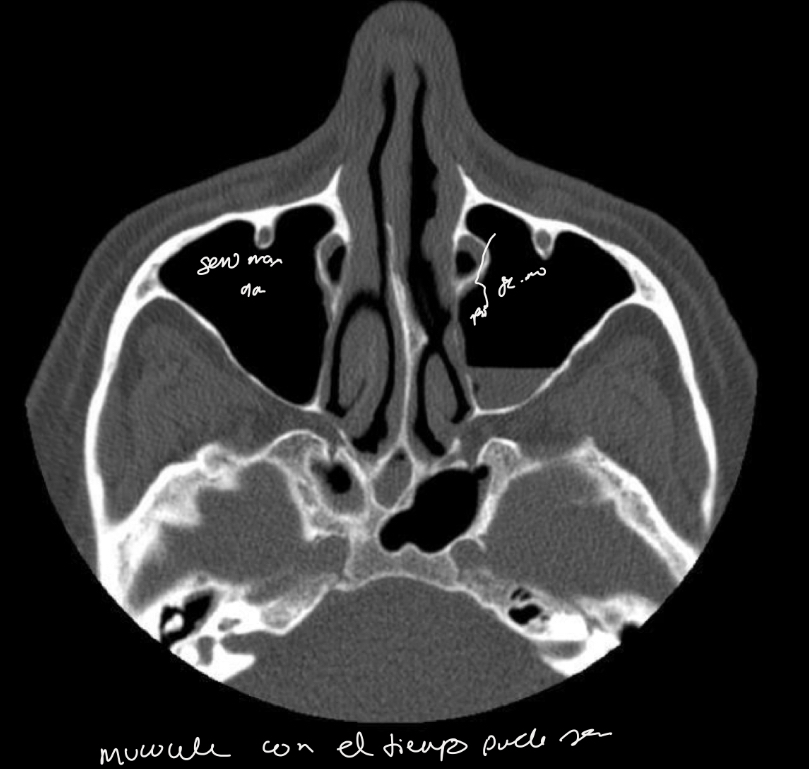

Q se pide en rx

A

serie SPN ap, lateral waters boca abierta

Mejor metodo imagen

tc

q se ve en tc

engrosamiento mucosa periferica

Niveles hidroaereos

Permite evaluar oclusion osteomeatal

Desviacion septum

Engrosamiento cornetes:rinitis

Con el tiempo se puede hacer mucocele

si